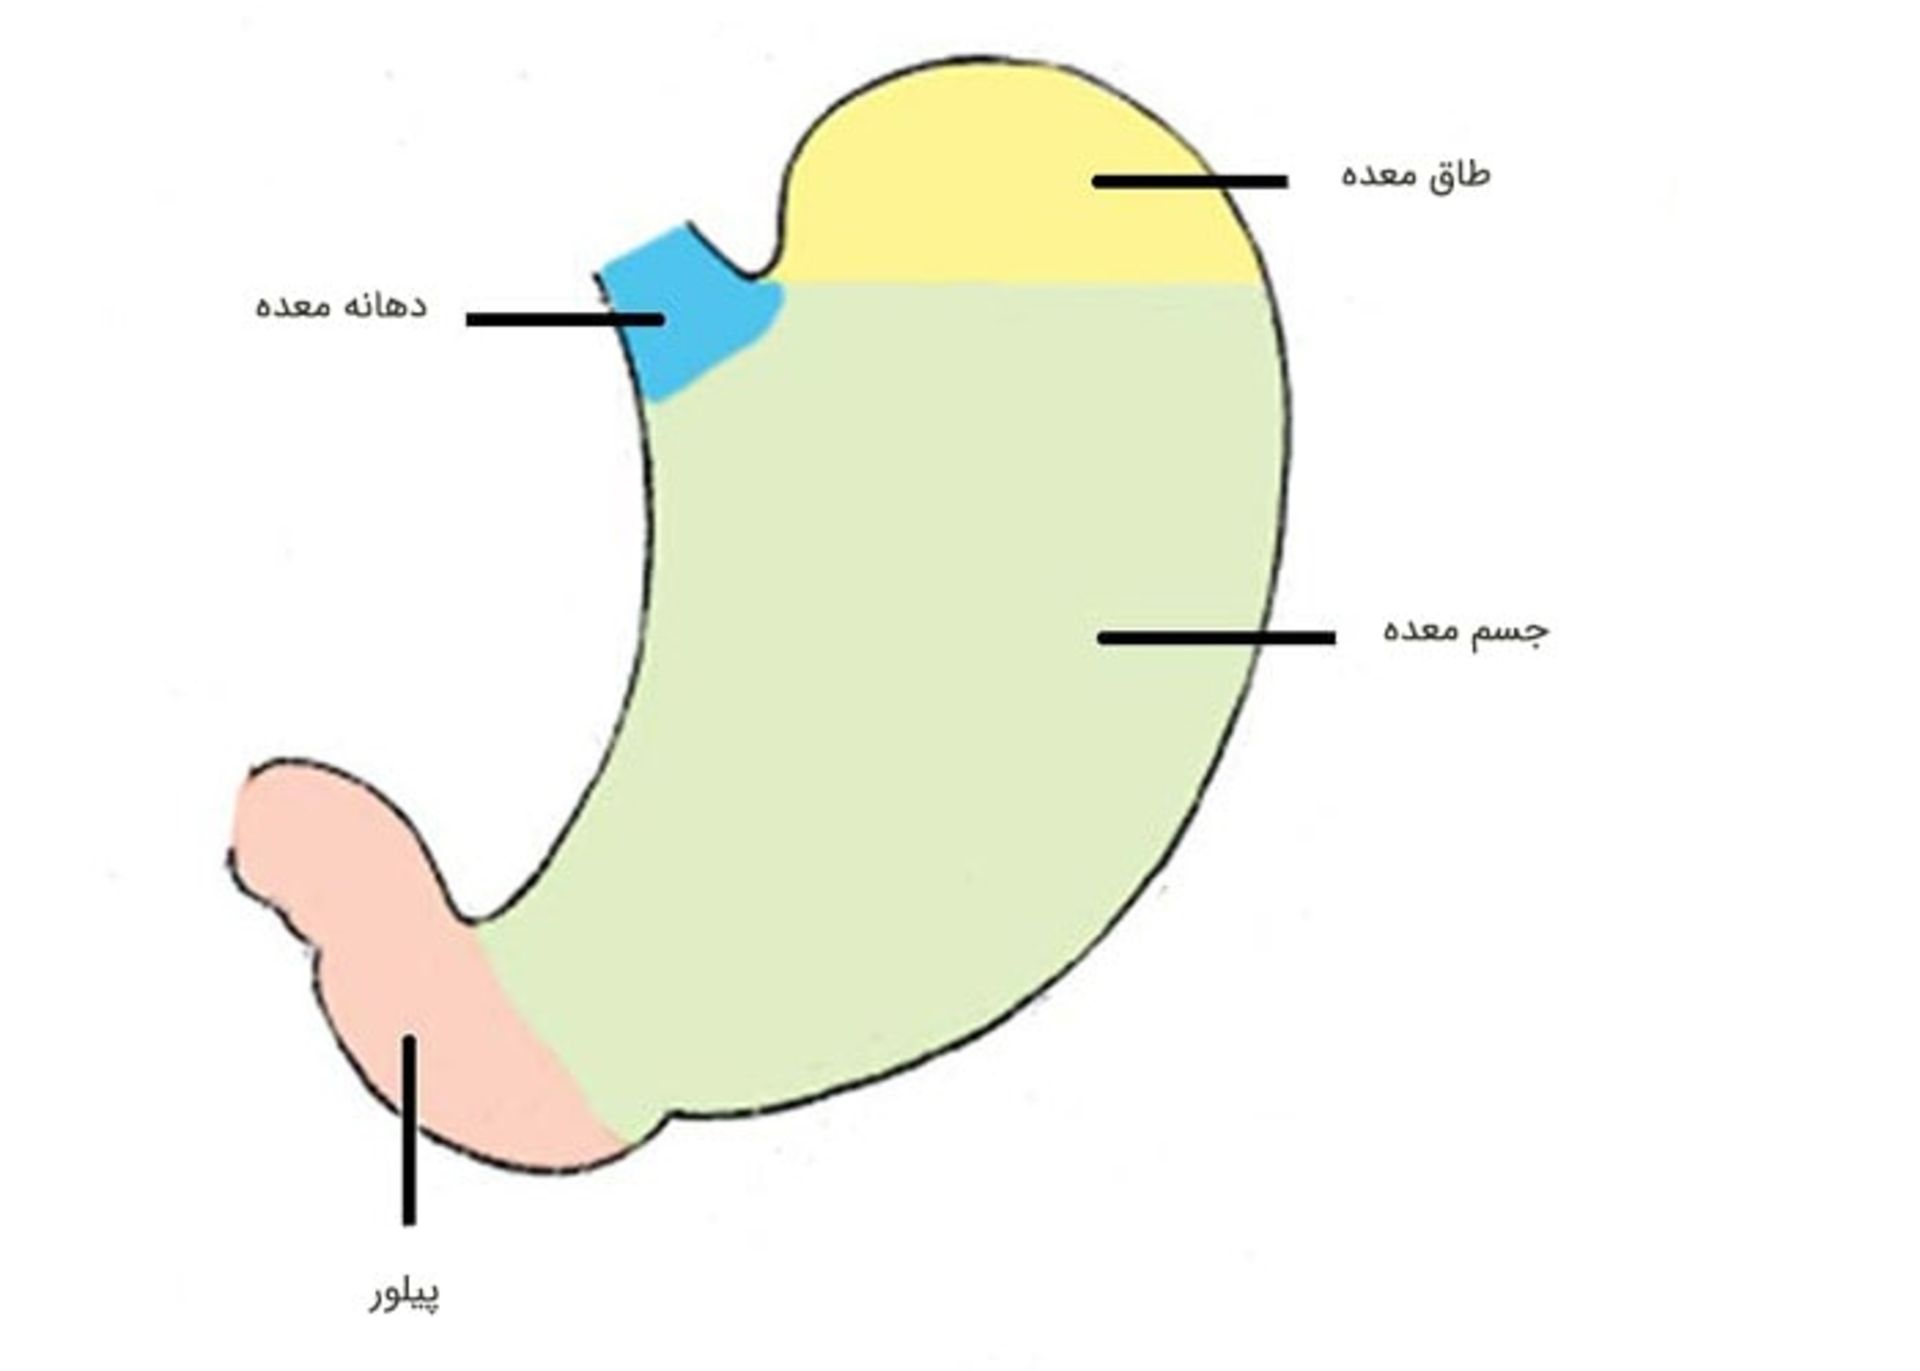

ساختار معده

غذا بعد از اینکه جویده و قورت داده میشود، وارد مری میشود. مری لولهای است که غذا را به معده میرساند. مری در ناحیهی اتصال مری به معده، به معده میپیوندد. معده اندام کیسهمانندی است که غذا را در خود نگه میدارد و با ترشح شیرهی معده به هضم آن کمک میکند. در معده، غذا با شیرهی معده مخلوط میشود و سپس به اولین بخش از رودهی کوچک که دوازدهه نام دارد، وارد میشود. معده از پنج قسمت تشکیل شده است:

دهانهی معده: نخستین بخش از معده که نزدیکترین فاصله با مری را دارد.

طاق معده: بخش فوقانی معده که نزدیک دهانهی معده قرار گرفته است.

جسم معده: بخش اصلی معده که بین بخشهای فوقانی و تحتانی قرار گرفته است.

آنتروم: بخش تحتانی معده (نزدیک رودهی کوچک) که غذا در آن با شیرهی معده مخلوط میشود.

پیلور معده: آخرین بخش از معده که همچون دریچهای برای کنترل تخلیهی محتویات معده به داخل رودهی کوچک عمل میکند.

سه بخش اول معده (دهانه، طاق و جسم معده) گاهی «معدهی نزدیک» نامیده میشود. برخی از سلولهای موجود در این بخش از معده، اسید و پپسین (یک آنزیم گوارشی) تولید میکنند که به هضم غذا کمک میکنند. آنها همچنین پروتئینی به نام فاکتور داخلی را تولید میکنند که بدن برای جذب ویتامین B12 به آن نیاز دارد. دو بخش تحتانی معده (آنتروم و پیلور)، «معدهی دور» نامیده میشود. اندامهای دیگری که در نزدیکی معده قرار گرفتهاند عبارتاند از رودهی بزرگ، کبد، طحال، رودهی کوچک و پانکراس. دیوارهی معده از پنج لایه تشکیل شده است: